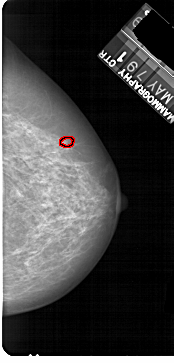

A_1894_1.RIGHT_CC

FILE: A_1894_1.RIGHT_CC.OVERLAY

TOTAL_ABNORMALITIES 1

ABNORMALITY 1

LESION_TYPE CALCIFICATION TYPE PLEOMORPHIC DISTRIBUTION CLUSTERED

ASSESSMENT 4

SUBTLETY 2

PATHOLOGY MALIGNANT

TOTAL_OUTLINES 1

BOUNDARY